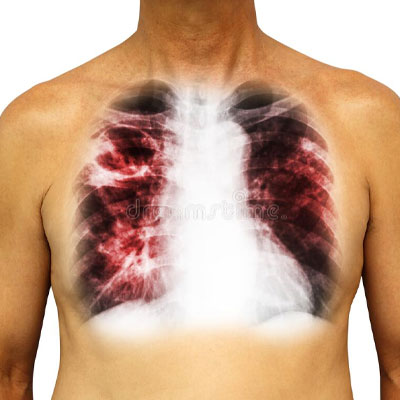

Consultation of ILD from interventional pulmonology doctors in Hyderabad at lung hospitals depends on the type of diagnosing and severity. So, its consultation generally includes, relieving symptoms, improving quality of life, and slowing disease progression.

Whereas, if ILD is developed in pulmonary hypertension then doctors at chest medicine hospitals in Hyderabad consult treatment from supportive therapy or PH-specific therapy